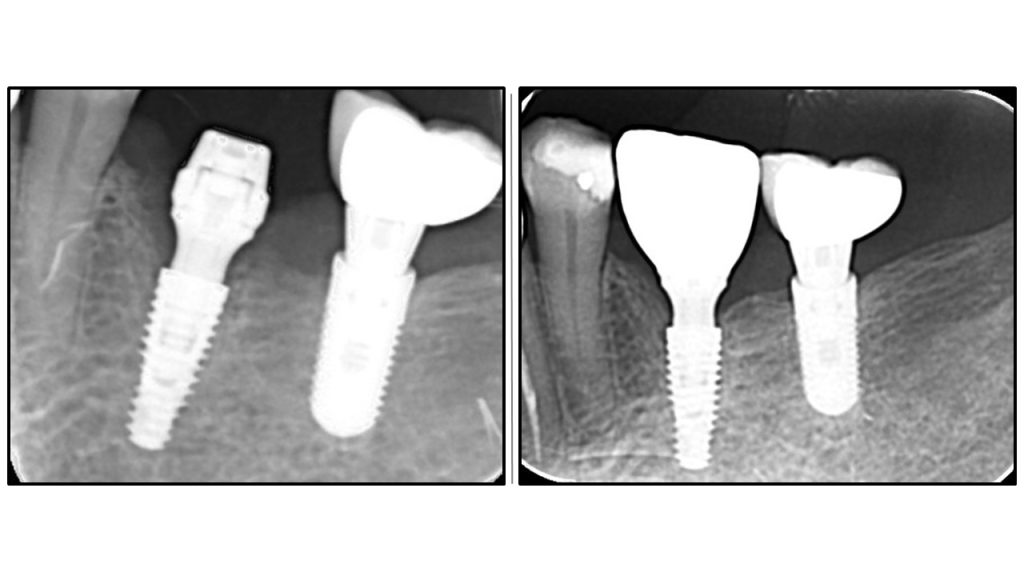

Радиографска анализа: стабилност костине крошне